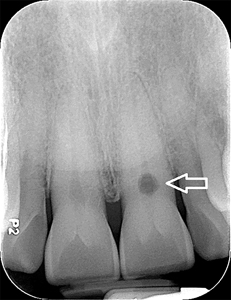

Root Canal Treatment of Maxillary Premolars With Three Roots: A Case Series

Cunha Fig 3b alternate text for this image

Abstract The successful outcome of endodontic treatment depends on an appreciation of the internal and external tooth morphology. Teeth with unusual root canal anatomy present a unique challenge even to experienced clinicians. This case series describes the endodontic treatment of maxillary premolars with three root canals. The identification and management of this uncommon anatomical variation of the … Read more